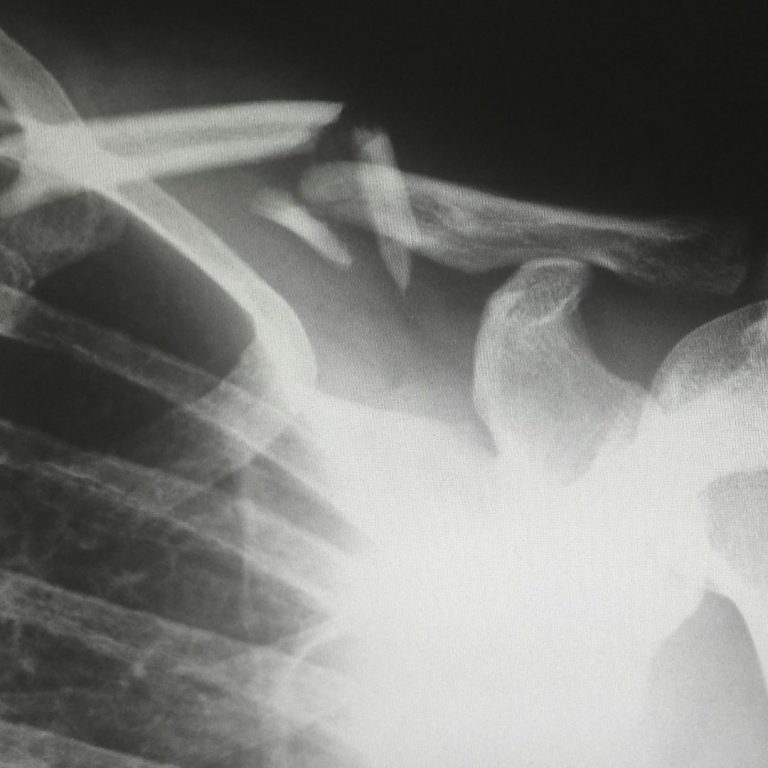

Fracture

Instabilité / Luxation

Disjonction Acromio-claviculaire